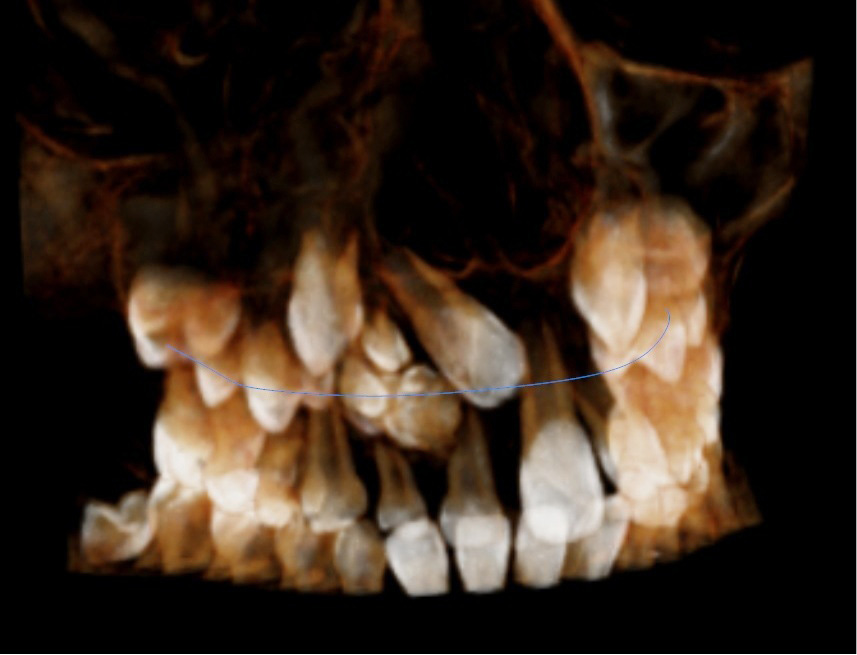

STRESZCZENIE: Zębiaki są najczęstszymi guzami zębopochodnymi jamy ustnej stanowiącymi 21-67% tych nowotworów. Klasyfikacja guzów głowy i szyi opublikowana przez Światową Organizację Zdrowia w 2017 roku uważa te zmiany za guzopodobne, zbudowane z tkanek twardych i miękkich zęba. Jednym z najczęstszych objawów związanych z zębiakami są zaburzenia w wyrzynaniu zębów. W wielu przypadkach brak wyrzynających się zębów stałych przedniego odcinka szczęki jest pierwszym objawem zmiany, dlatego też we wszystkich tego typu przypadkach niezbędna jest precyzyjna i wczesna diagnostyka. Dokładna wiedza dotycząca terminów wyrzynania zębów jest konieczna dla lekarza dentysty w celu wczesnego uchwycenia odstępstw od normy i określenia przyczyn takiego stanu. W pracy przedstawiono opis przypadku 9-letniego pacjenta z zębiakiem w obrębie szczęki.

SUMMARY: Odontomas are the most common odontogenic tumours of the oral cavity accounting for 21-67% of these tumors. The Classification of Head and Neck Tumors published in 2017 by the World Health Organization considers these lesions to be hamartomes or tumour-like lesions made of the hard and soft tissues of a tooth. One of the most common symptoms associated with odontomas are tooth eruption disorders. [...]